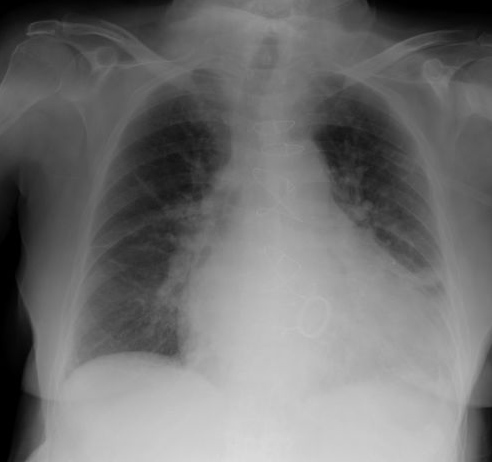

Neumonia basal derecha.

Neumonía basal derecha.